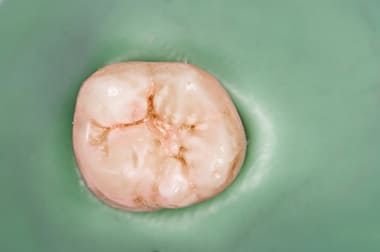

ラバーダムとは根管治療の際に歯に装着するゴムのことです。ゴムを拡げて口を覆い隠し、治療する歯だけをゴムの外側に出して治療ができるため、治療中に根管内に細菌感染を防ぐことができます。

- ラバーダム